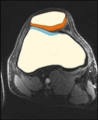

- analysis of cartilage thickness for ostheoarthitis assessment

- patellofemoral joint (prospective motion correction)

- depicted image is a healthy volunteer

- cf. CARS 2016 submission